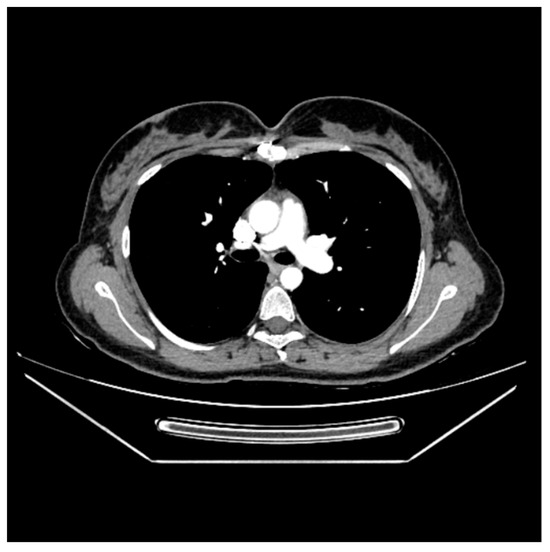

Swinging Mass Through the Pulmonary Valve: A Rare Case of Right Ventricular Myxoma

Primary cardiac tumors are rare, with an estimated incidence of 0.001% to 0.3% in autopsy series. Most are benign, the most common being cardiac myxomas, which typically originate in the left atrium. Right ventricular myxoma is among the rarest primary cardiac tumors, and its true incidence is difficult to determine, as most data come from isolated case reports. This paper aims to report a case of right ventricular myxoma in a young woman with a history of childhood malignancy and to discuss the possible association between the two conditions. Echocardiography, thoracic computed tomography (CT), and pulmonary CT angiography were used to assess the presence, location, and size of the tumor. The definitive diagnosis was established by histopathological examination. A 34-year-old woman, with a past medical history of acute lymphoblastic leukemia (ALL) in childhood, presented with a dry cough and exertional dyspnea persisting for three weeks. Transthoracic echocardiography revealed a mass located in the right ventricular outflow tract (RVOT), attached near the tricuspid valve and intermittently prolapsing into the pulmonary trunk. CT imaging confirmed the presence of the tumor in the RVOT and the main pulmonary artery. Because of the high risk of massive pulmonary embolism, the patient underwent urgent surgical excision of the tumor. Histopathological analysis confirmed the diagnosis of cardiac myxoma. The postoperative recovery was uneventful, and the three-month follow-up showed no recurrence or signs of pulmonary embolism. The patient’s history of ALL raised the question of a possible association; however, a review of the literature revealed no previously reported link. In conclusion, right ventricular myxomas are extremely rare. The occurrence of cardiac myxoma in this patient following childhood ALL appears to be incidental. Further research is needed to determine whether ALL survivors have an increased predisposition to subsequent cardiac tumors. Full article

Show Figures

Figure 1